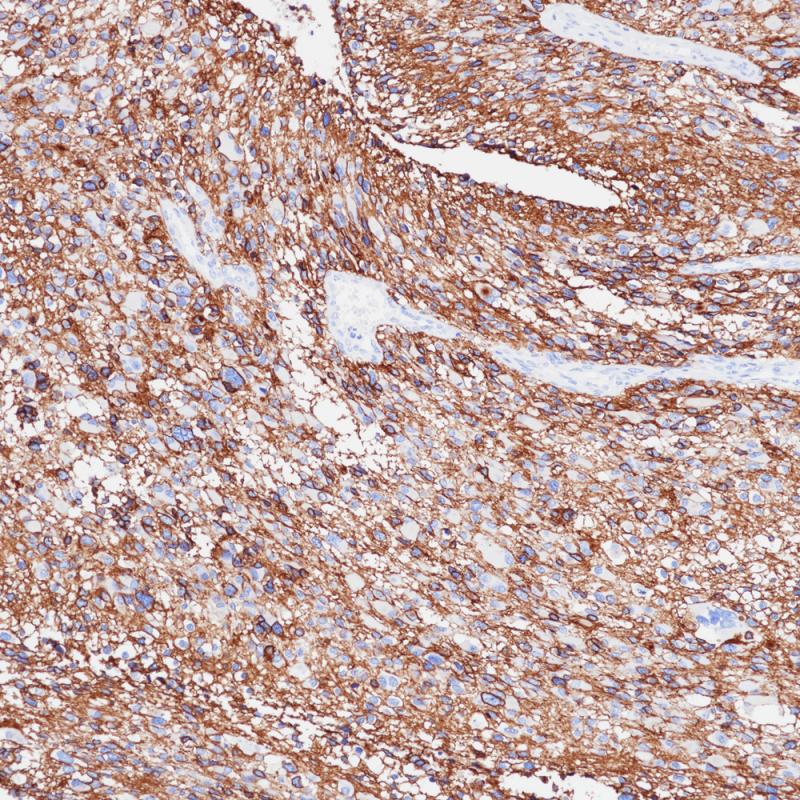

子宫内膜癌p16(BPM6238)染色

p16 INK4A(p16)是一种细胞周期蛋白依赖性激酶(CDKs)抑制剂,参与细胞周期的调控。当P16 INK4A基因发生缺失、突变等,不能抑制CDK4,最终导致细胞进入恶性增殖,加速肿瘤发生。p16 INK4A主要响应致癌基因表达、染色质断裂和各种压力胁迫等事件,这有利于受损细胞几乎无一例外地被衰老程序所捕获。因此,p16 INK4A的表达是常用的衰老细胞标志物。另外,p16 INK4A蛋白的高表达可作为宫颈癌细胞中的预测性生物标志物。

阳性对照

宫颈上皮内瘤变

亚细胞定位

细胞核